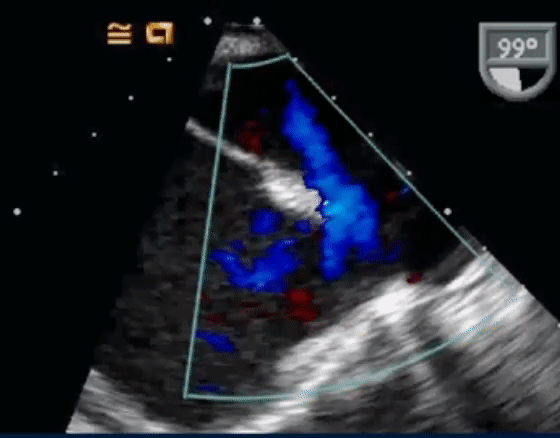

- The following TEE with color Doppler shows a jet of MR going into the LA and RA

- On Color Doppler, we see the blue flow going from LA to the RA through the superior sinus venosus defect: